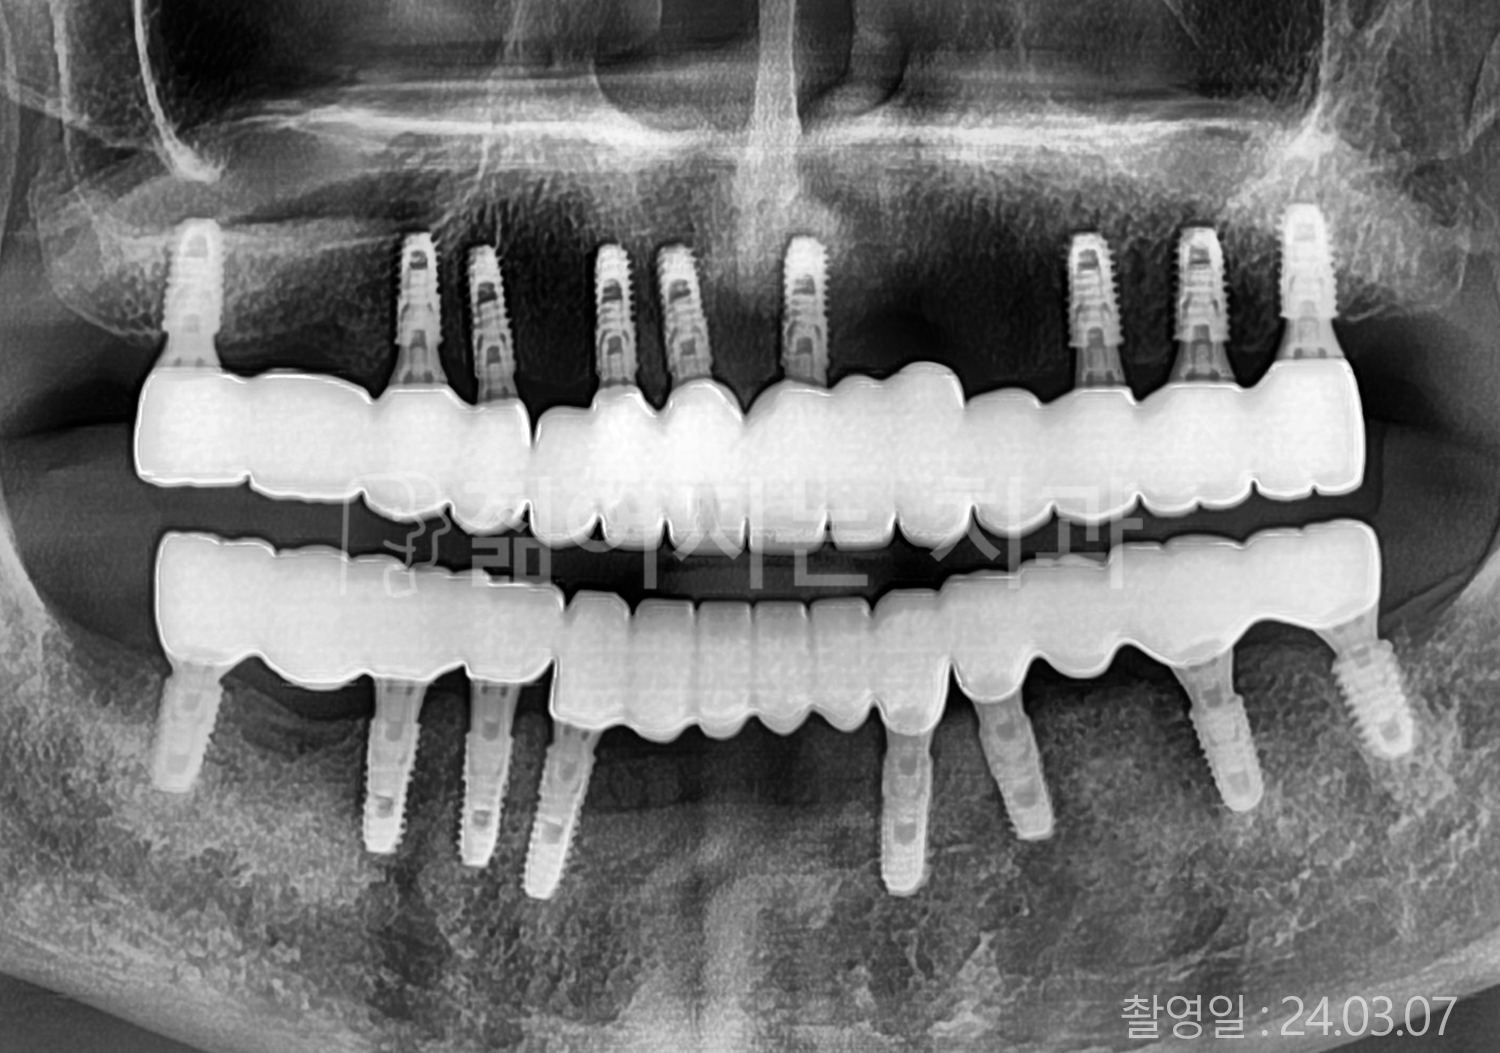

• 70대 고혈압, 당뇨 전체치아 10개 이상 임플란트

• 50대 고혈압, 당뇨 전체치아 10개 이상 임플란트

• 60대 고혈압, 당뇨 전체치아 10개 이상 임플란트

• 50대 전체치아 10개 이상 임플란트

• 70대 당뇨 전체치아 10개 이상 임플란트

• 80대 전체치아 10개 이상 임플란트

• 40대 전체치아 10개 이상 임플란트

• 60대 고협압, 고지혈증 전체치아 10개 이상 임플란트

• 60대 전체치아 10개 이상 임플란트